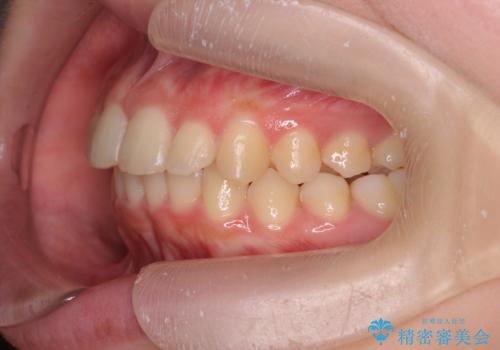

- 突出感のある、前歯の矯正治療を求めて来院されました。

軽度な突出・ガタつきを26枚・約半年の矯正治療期間で計画するインビザラインモデレートプランで治療を始めて行きます。

約半年といった短期間で、前歯の角度やガタつきを改善することができました。